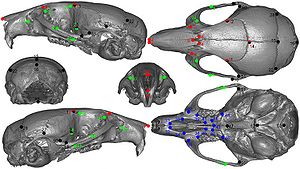

Publication: Front Zool. 2015 Dec 1;12:33. PMID: 26628903 | PDF Authors: Young R, Maga AM. Institution: Center for Developmental Biology and Regenerative Medicine, Seattle Children's Research Institute, Seattle, WA, USA. Background/Purpose: Here we present an application of advanced registration and atlas building framework DRAMMS to the automated annotation of mouse mandibles through a series of tests using single and multi-atlas segmentation paradigms and compare the outcomes to the current gold standard, manual annotation. Results: Our results showed multi-atlas annotation procedure yields landmark precisions within the human observer error range. The mean shape estimates from gold standard and multi-atlas annotation procedure were statistically indistinguishable for both Euclidean Distance Matrix Analysis (mean form matrix) and Generalized Procrustes Analysis (Goodall F-test). Further research needs to be done to validate the consistency of variance-covariance matrix estimates from both methods with larger sample sizes. Conclusion: Multi-atlas annotation procedure shows promise as a framework to facilitate truly high-throughput phenomic analyses by channeling investigators efforts to annotate only a small portion of their datasets. Funding:

Visualization of the distances between the atlas surface that was landmarked (p90) and four other surfaces constructed. a 50 % Probability surface (p50); b 70 % Probability surface (p70); c Surface thresholded at grayscale value of 35. d Surface thresholded at grayscale value of 55. RMS: Root mean square error. Segmented left hemi-mandibles were imported into 3D Slicer and visualized using a fixed rendering and threshold setting. |